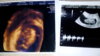

Ostatnie usg następne za 6 dni mam nadzieję że poznam płeć obecnie 13 tc

Załączniki

• DSC_0058.JPG

563,7 KB · Wyświetleń: 115